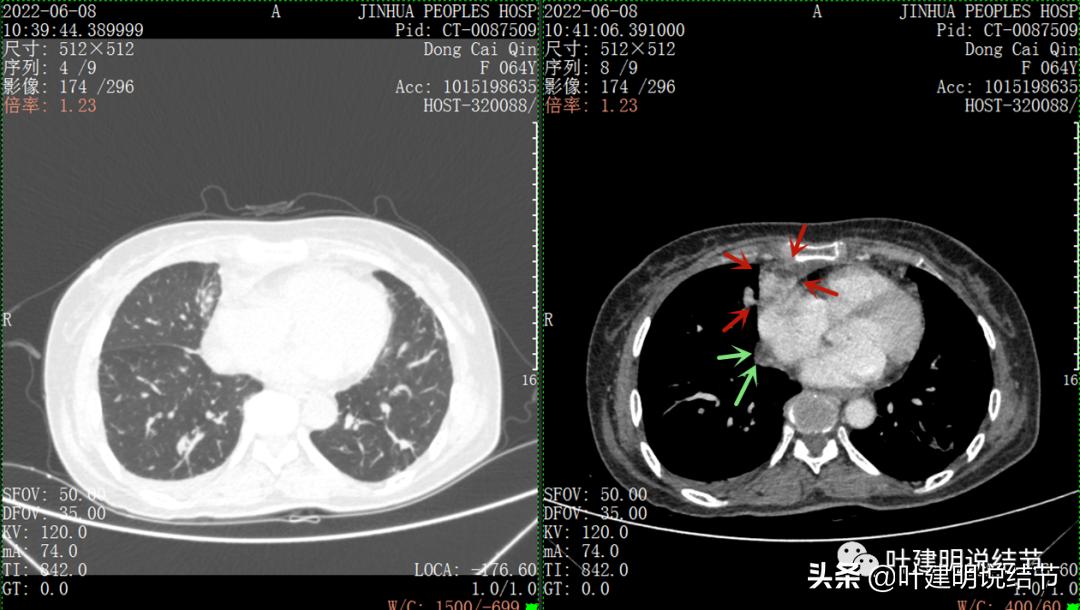

再来看看她的CT增强图像:

以下图片左侧是肺窗,右侧是纵隔窗。红色箭头示病灶,桔色箭头示无名静脉,黄色箭头示支气管,砖色箭头示上腔静脉,蓝色箭头示主动脉,紫色箭头示肺动脉。

绿色箭头示近膈面处,心脏边病灶

此灶与主病灶不是完全相连的